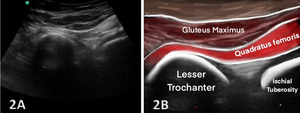

To ensure consistent and accurate evaluation of the IFS and surrounding structures, a standardized scanning protocol should be followed. Typically, the patient is positioned either in a prone or lateral decubitus position, with the hip in neutral or slight extension and external rotation to optimize visualization of the ischiofemoral region.

Transverse View: The ultrasound transducer is placed transversely across the gluteal region, oriented to visualize both the ischial tuberosity and the lesser trochanter. This view allows for direct measurement of the IFS and identification of the quadratus femoris muscle.

Longitudinal View: The probe is also oriented along the long axis of the quadratus femoris muscle to evaluate for signs of edema, atrophy, or tendinopathy within the muscle, which are commonly associated with IFI.

By adhering to these protocols, MSKUS provides a detailed and dynamic evaluation of the IFS, enabling clinicians to assess anatomical variations and soft tissue changes that contribute to IFI, thereby improving diagnostic accuracy and guiding treatment decisions.